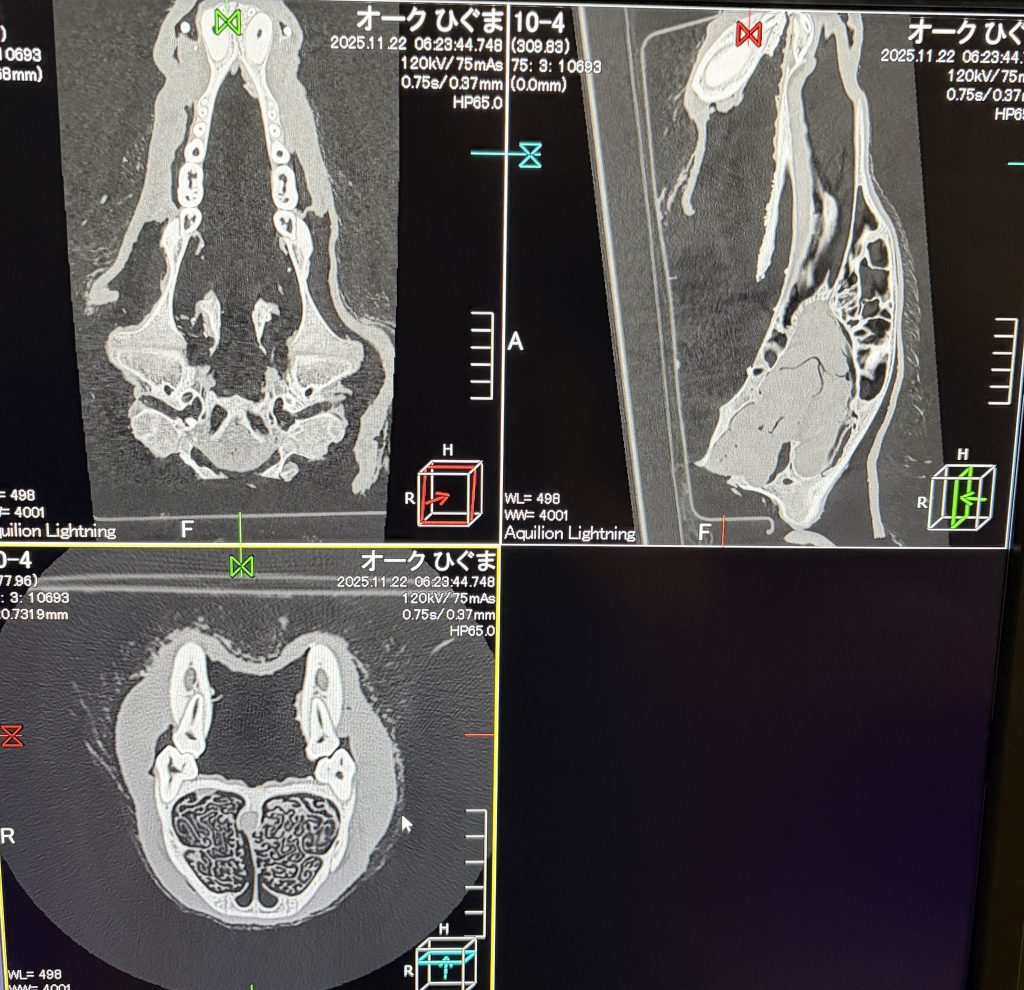

レントゲンに続き、CT検査

健康なヒグマです

というような骨です💦

bear CT scan

it is so hard and durable,tough